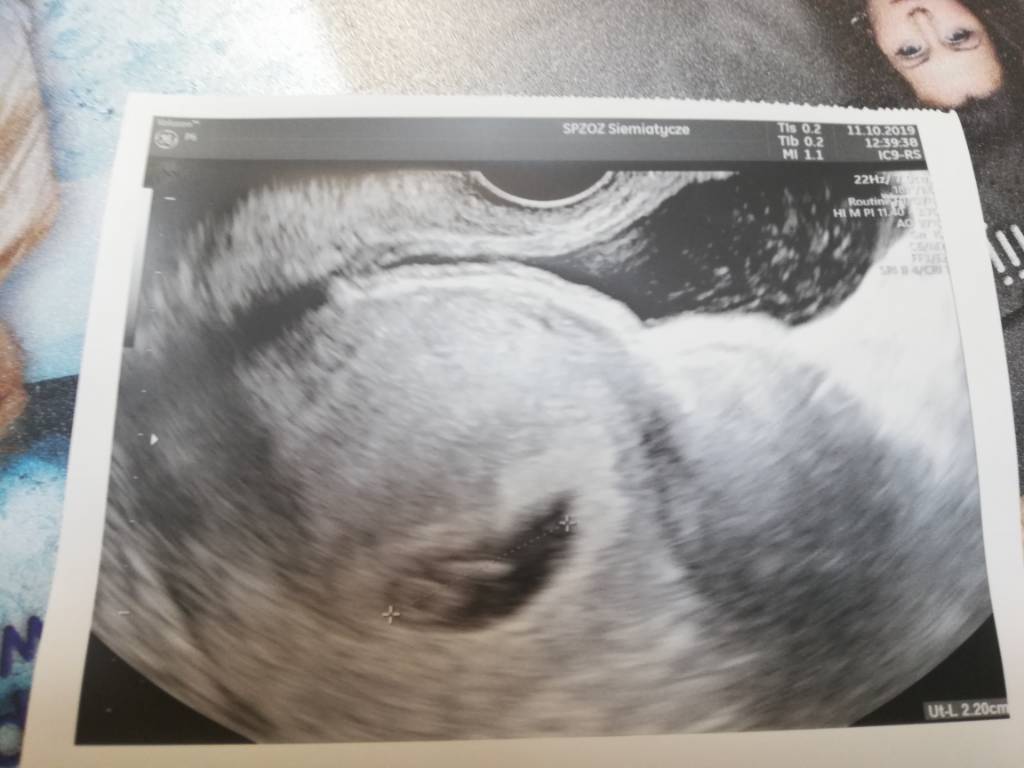

Ja też dziś po wizycie, wg Om 7+0. Nie wiem dokładnie co jest na tym USG, moze wy wiecie?bo lekarz trochę mimoza a poszłam do niego bo chciałam już dziś potwierdzić. Ale bardzo się cieszę bo poprzednim razem dwa lata temu było puste jajo plodowe.

No ja widzę piękny zarodek tylko jakoś słabo opisane te wymiary. Ale na pewno jest dobrzegratulacjeJa też dziś po wizycie, wg Om 7+0. Nie wiem dokładnie co jest na tym USG, moze wy wiecie?bo lekarz trochę mimoza a poszłam do niego bo chciałam już dziś potwierdzić. Ale bardzo się cieszę bo poprzednim razem dwa lata temu było puste jajo plodowe.